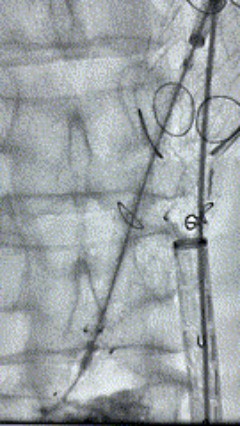

6. 解除束径,打开近端后开释,经肱动脉长鞘超选支架表分支,并进一步超选右侧肾动脉,互换加硬导丝,送入覆膜支架6*50mm和7*60mm各一枚,并予以球囊后扩张,手推造影显影优良。

7. 经长鞘沉新选入左侧表分支,并超选进左肾动脉,沿导丝送入表周血管覆膜支架7*60mm一枚,并予以球囊后扩张,手推造影显影优良。

8. 从右侧股动脉入路送入腹主支架AB-24-12-110-S,近端沉叠胸腹自动脉支架远端,调整好支架地位后开释。

9. 经左股动脉送入导丝导管,超选进腹自动脉支架短腿内,后沿导丝送入髂支,同理,右侧沿导丝送入髂支并开释,使用俄罗斯贵宾会集团适应性球囊后扩各支架衔接处及支架近远端,最后通过预留导管向瘤腔注入人纤维蛋白粘合剂数支,造影显示分支畅达。